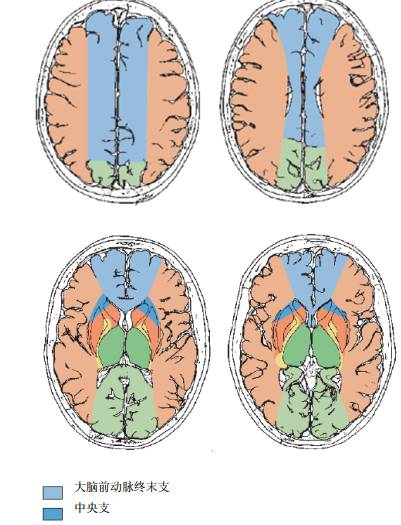

对于我们日常临床操作中,更有用的恐怕不是上面的解剖知识,而是如下图2所示的轴位供血区分布图。大脑前动脉的供血区相对而言比较简单直接,主要包括大脑半球内侧面前3/4和额顶叶背侧面上1/4皮质和皮质下白质,深穿支的主要供血区为内囊膝部和后肢前2/3,壳核、苍白球和尾状核。

图2 大脑前动脉供血区(轴位)